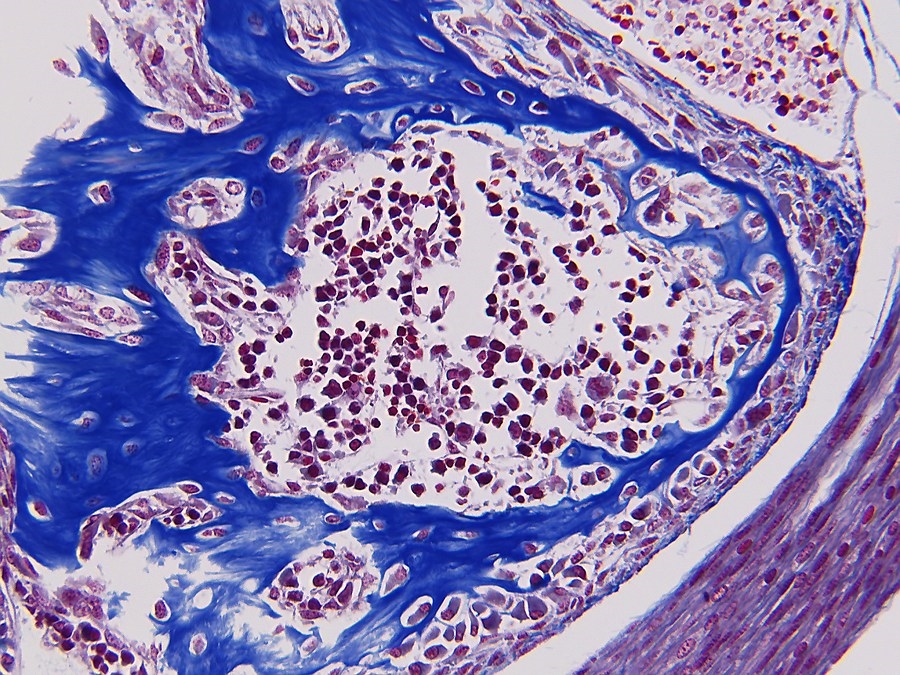

Knochenbildung mit Blutzellbildung, Objektiv Leitz Plan Fluotar 25x.

Sagittaler Schnitt von ein fünf tagen alte Maus. Schnittdicke 4µm.

Knochen werden Rot angefärbt. Färbung: Phosphorwolframsäure-Hämatoxylin (PTAH).